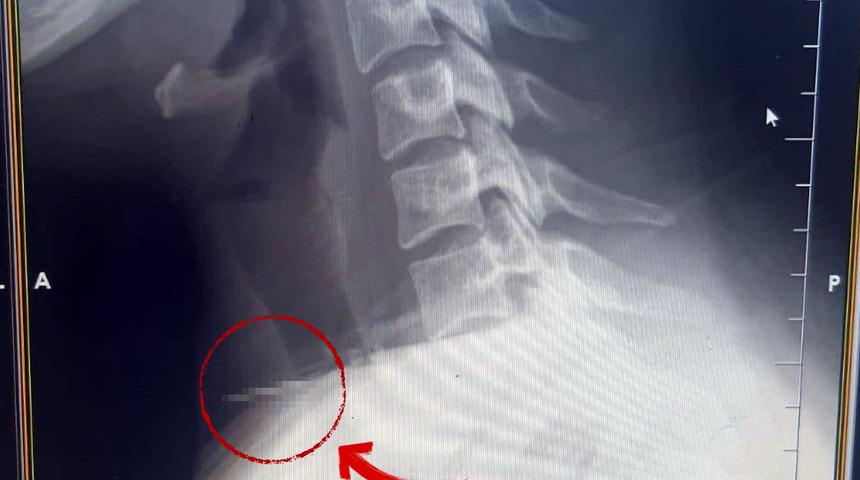

Radyolojik incelemeler ve klinik değerlendirmeler sonucunda, 3 santimetrelik iğnenin boğaz bölgesinin derinliklerine doğru ilerlediği tespit edildi. İğne, yaklaşık 1 saat süren ameliyatla çıkarıldı. Ameliyat sonrası süreci sorunsuz atlatan hasta taburcu edildi.